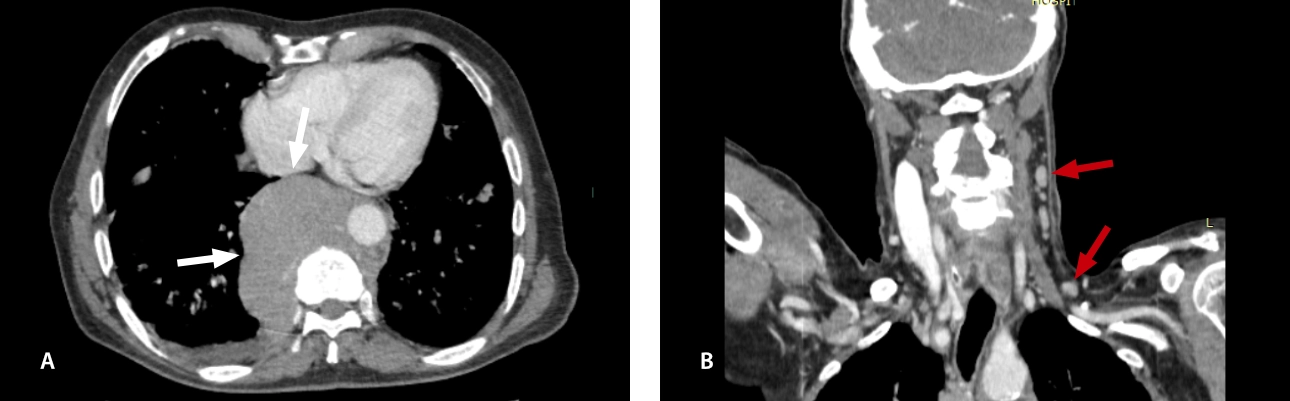

Fig 6: Retroperitoneal lymph node cluster: (A) US shows hypodense grayscale lymph node cluster (white arrow) with color/Power Doppler conserved vascularity (dashed arrow). (B) Contrasted CT scan shows retroperitoneal lymph node conglomerate with faint enhancement on contrast agent (red arrows).

lymphoma-simulator-fig7-pc

Fig 7: Contrasted CT scan: coronal reconstruction (A) axial section (B) shows heterogeneous parotid glands enlarged (red arrows).

lymphoma-simulator-fig8-pc

Fig. 8: Contrasted CT scan: (A) axial section (B) coronal reconstruction: shows heterogeneous lacrimal glands, enlarged in size (red arrows).

lymphoma-simulator-fig9-pc

Fig. 9: Contrasted CT scan: (A) axial section shows paravertebral conglomerate (bulky mass) (white arrows), (B) coronal reconstruction shows bilateral cervical lymphadenopathy (black arrows).